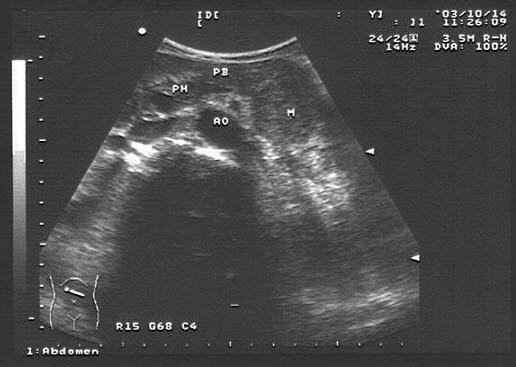

46、单项选择题

患者,消瘦,于左上腹触及一包块,超声见一大小5×7cm的呈假肾征的光团,如图所示,考虑为()

A.胰腺癌